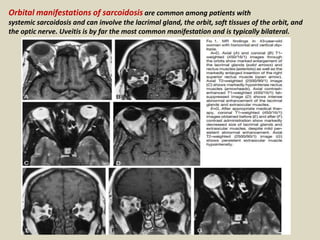

Orbital manifestations of sarcoidosis are common among patients with

systemic sarcoidosis and can involve the lacrimal gland, the orbit, soft tissues of the orbit, and

the optic nerve. Uveitis is by far the most common manifestation and is typically bilateral.

Lacrimal gland involvement: The lacrimal gland is rarely involved in sarcoidosis.

Imaging features on computed tomography (CT) scan include bilateral, asymmetric enlargement

with intense enhancement of the lacrimal gland. The gland maintains its anatomic configuration. A

portion of the gland may extend medially along anterior border of the globe. MR demonstrates

hypointense T1 and T2 signal within enlarged glands that also show intense enhancement.